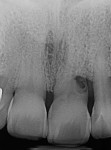

A healthy 71-year-old male patient presented with advanced periodontal disease and pain on the maxillary left central incisor. Upon radiographic analysis, an external root resorption was diagnosed, which caused gingival recession and a cortical bone defect on the facial aspect of the tooth (Figure 1 and Figure 2). Proximal bone volume and the distal interproximal papilla were compromised. Digital implant planning and surgical guide fabrication were done to facilitate precise implant placement (Figure 3).